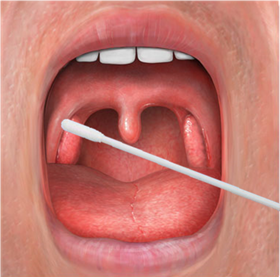

口咽拭子

“由于口咽拭子张口就能进行操作,相对简单,因此临床上比较常用,但取样者暴露的风险更高。”蔡跃新说。

据梁发雅介绍,虽然经口取样的口咽拭子最为常用,但这一操作也是一个高风险操作,操作者往往需要正对患者口腔,采集过程中患者容易出现刺激性干咳、呕吐等症状使采集者暴露在带病毒的气溶胶中。